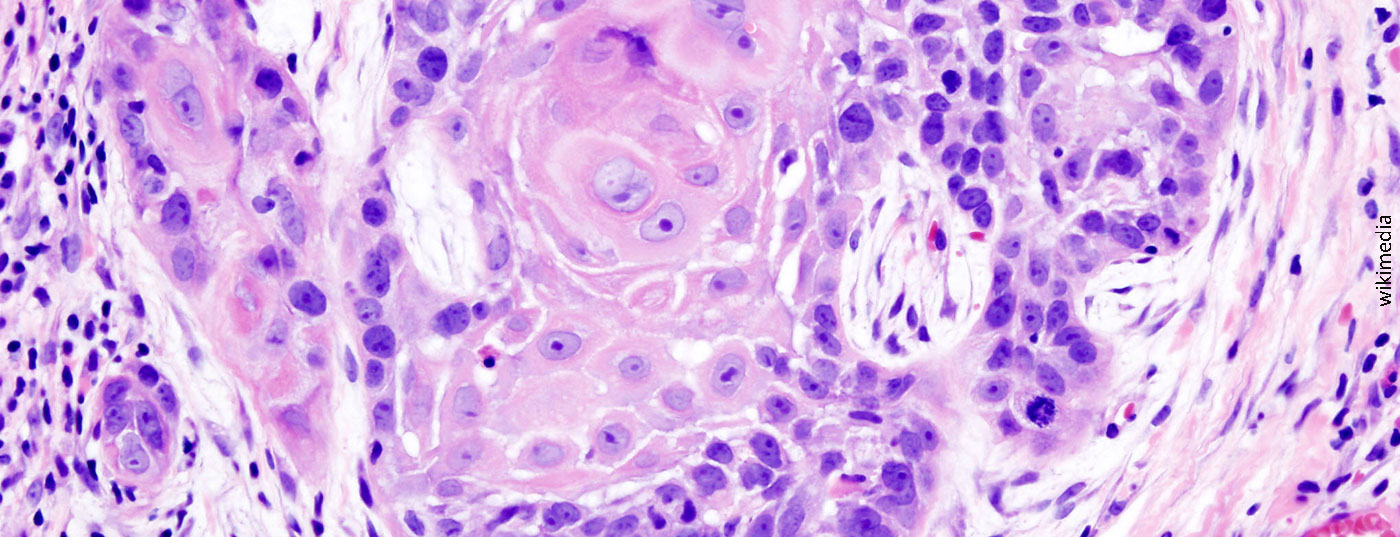

The phase III KEYNOTE-048 trial presented at the ASCO 2019 annual meeting evaluated the PD-1 (programmed cell death 1 protein) inhibitor pembrolizumab (KEYTRUDA®) both as monotherapy and in combination with chemotherapy for first-line treatment of recurrent or metastatic head and neck squamous cell carcinoma (HNSCC). This is the first publication of data from this study on overall survival with pembrolizumab in combination with chemotherapy as a function of tumor PD-L1 expression and from the pembrolizumab monotherapy arm in the overall collective and independent of tumor PD-L1 status. The interim analysis was presented at the ESMO 2018 Annual Meeting. This showed superior overall survival with pembrolizumab in combination with chemotherapy in the overall population as well as with pembrolizumab monotherapy in patients whose tumors expressed PD-L1 with a combined positive score (CPS) ≥20 and ≥1 compared to patients on the current standard of care (EXTREME regimen). Squamous cell carcinomas are classified according to the currently valid TNM systems of the Union internationale contre le cancer (UICC) or the American Joint Committee on Cancer (AJCC). According to the AJCC, squamous cell carcinomas of the neck-head region are distinguished from those of other localizations.